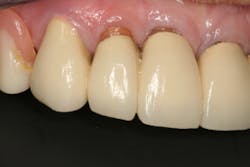

Dentition: Upper anterior splinted crowns had open margins and caries. Radiographs confirm decay, along with open margins (figures 6–11). Lower incisal anterior wear noted (figure 2).

Periodontium: Probing depths normal on all teeth, with some bleeding noted around the margins of the upper splinted crowns. Slight to moderate bone loss on lower anterior teeth.

The occlusion needed to be changed to a more desirable one, as well as improve the esthetics. After examining all of the findings, options were presented to the patient for the final restorative outcome. Because of a limited budget, the patient preferred to have the remaining maxillary teeth removed and an immediate maxillary denture placed. As a result, a new plane of occlusion needed to be predictably determined and clearly communicated to the laboratory technician.